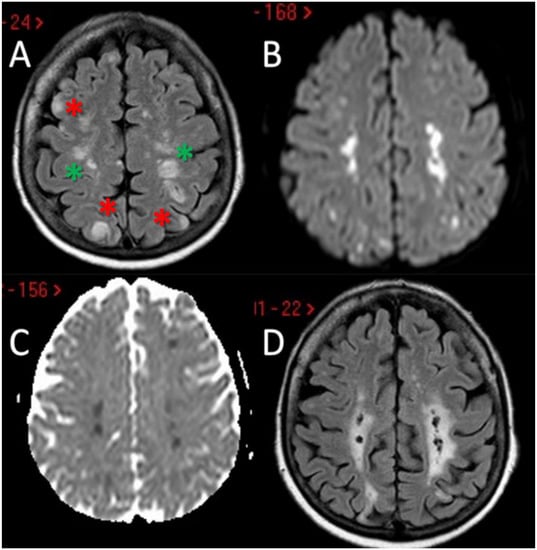

The first patient is a 55-year-old man who was first admitted to the Emergency Department after the acute onset of confusion, altered speech comprehension and production. The episode lasted 45 min and spontaneously resolved. Head CT and neurosonological examination of the neck and cerebral vessels were unremarkable, and the patient was discharged on single antiplatelet therapy (acetylsalicilic acid) with a diagnosis of transient ischemic attack (TIA). He went back to the hospital two days later after developing writing difficulties, and he was admitted to our Stroke Unit; no further focal neurological deficits were evident on clinical examination. The most relevant aspects of his past medical history were mild hyperlipidaemia and smoking; recent lab tests performed before admission revealed an increase in the absolute and relative eosinophil count above the threshold for HES diagnosis. A second head CT at two days from the symptom onset showed an ischemic lesion involving the left parietal lobule and angular gyrus, confirmed by a Magnetic Resonance Imaging (MRI) scan (Figure 1A–D).

Figure 1. Brain MRI of the first patient. MRI of patient 1 showed the presence in the axial Fluid Attenuated Inversion Recovery (FLAIR) sequences of a wedge of cortical ischemic lesions in the left posterior parietal lobe (yellow asterisk) (A) with DWI and ADC sequences pattern suggesting acute ischemic lesions (B,C). MRA (time-of-flight [TOF] reconstruction) shows fully patent proximal intracranial arteries and right A1 anterior cerebral artery (ACA) aplasia (D). MRI: Magnetic Resonance Imaging; MRA: Magnetic Resonance Angiography; DWI: Diffusion Weighted; ADC: Apparent Diffusion Coefficient.